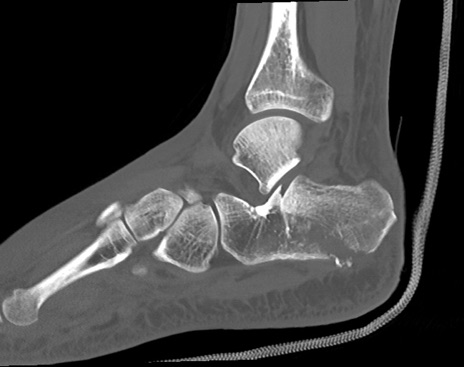

症例37 左足関節CT(矢状断像)

左足関節CT

冠状断像